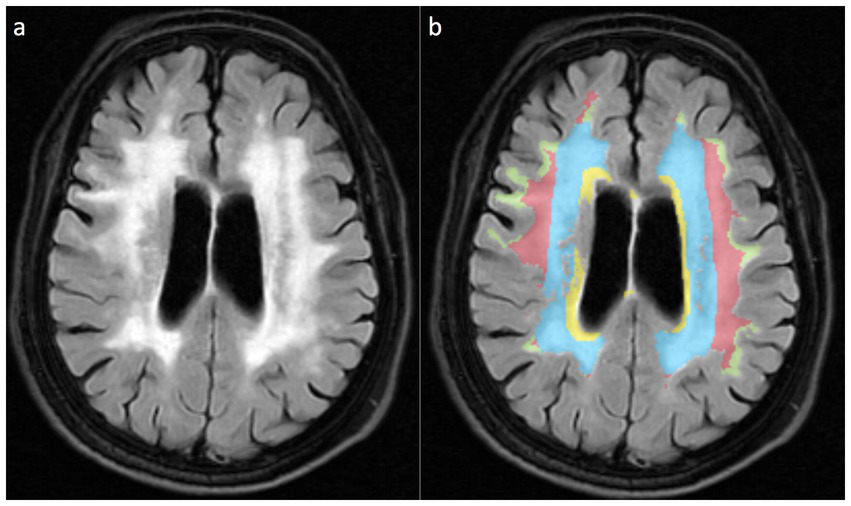

This study implemented a dual-modality imaging assessment framework: for semi-quantitative visual analysis, PWMH and DWMH were graded using the Fazekas scoring system (19). PWMH severity was stratified as mild (grade 0–1: focal punctate or early confluent lesions) versus moderate–severe (grade 2–3: confluent lesions involving >25% of the lateral ventricular body circumference), while DWMH severity was classified as mild (grade 0–1: scattered punctate lesions <5 mm in diameter) versus moderate–severe (grade 2–3: extensive confluent lesions or bridging phenomena). For volumetric topographical analysis, WMHs were segmented into four anatomically defined subregions (Figure 2): (1) Ventricular (≤3 mm from ventricular walls) representing lesions abutting the ependymal surface; (2) Periventricular (3–13 mm) depicting lesions paralleling ventricular orientation; (3) DWMH spanning transitional areas between periventricular and juxtacortical regions; (4) Juxtacortical (≤4 mm from cortex,) marking lesions along corticomedullary junctions. Among them, the Ventricular rim and Periventricular zone are collectively referred to as PWMH.

Figure 2

WMH is divided into four anatomical subregions based on the white matter topological localization system. (a) Schematic diagram of FLAIR sequences for different WMH subtypes; (b) Pseudo-color map corresponding to (a), with the Ventricular region marked in yellow, the Periventricular zone displayed in blue, the Deep brain white matter region shown in red, and the Juxtacortical region in yellow-green.